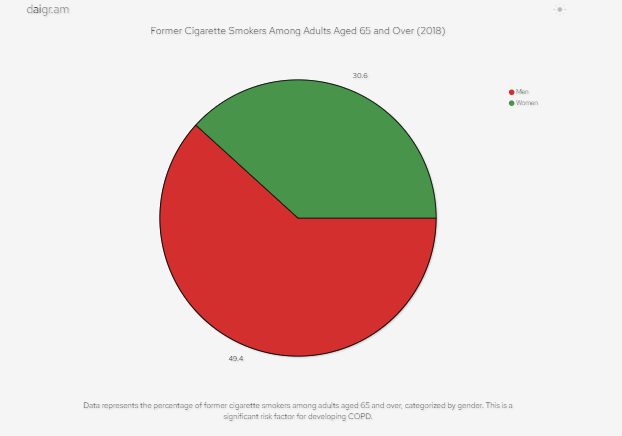

- 2018年,在65歲及以上的成年人中,49.4%的男性和30.6%的女性曾吸煙,這是罹患慢性阻塞性肺病的重要危險因素。